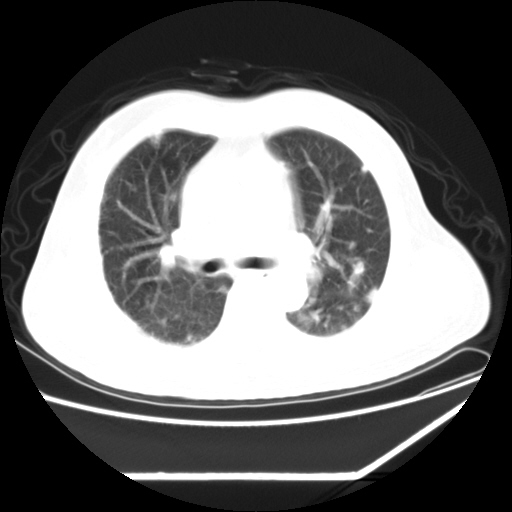

男,57,畏寒,发热

两侧多发肺脓肿,两侧胸膜增厚,抗炎治疗后复查

畏寒发热,首先考虑血源性肺脓肿,结合临床,抗炎后复查排除转移瘤等。

首先考虑血源性肺脓肿

1)考虑两肺感染性病变(金黄色葡萄球菌肺炎?);建议抗炎治疗后复查排除其他。2)双侧少量胸腔积液。